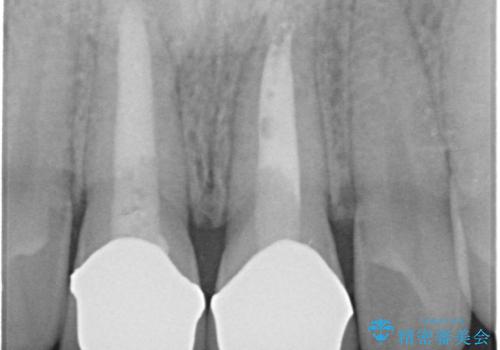

前歯の変色 神経のない歯の再治療

- 前歯の変色を気にして来院。

過去に神経の治療を行ったとのことでした。

特に右上の前歯の膿は大きくなって歯ぐきから排膿している状態でした。(フィステルといいます)

二本とも神経の治療のやり直し(再治療)を行ってからセラミックを入れています。